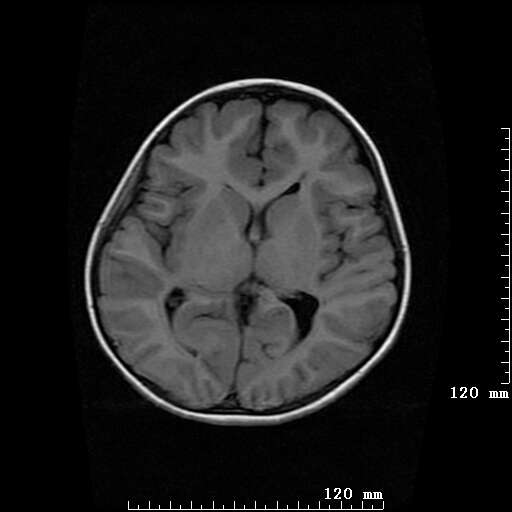

女,7岁,三岁才说话、走路。现智力尚可,走路不稳。临床怀疑大脑发育不全。

考虑 脑白质发育不良

脑折质变薄,双侧侧脑室稍扩张,支持考虑脑折质发育不良

侧脑室周围白质软化症。

考虑胼胝体发育不全,髓鞘形成不良。

支持考虑胼胝体发育不全,髓鞘形成不良。

脑裂畸形伴灰质异位

侧脑室周围白质数量减少,侧脑室不对称性扩大,左侧侧脑室后角呈方形改变,脑沟加深,结合临床考虑脑室周围白质软化症(pvl)。期待结果!

只看出灰质异位

支持脑白质发育不良。